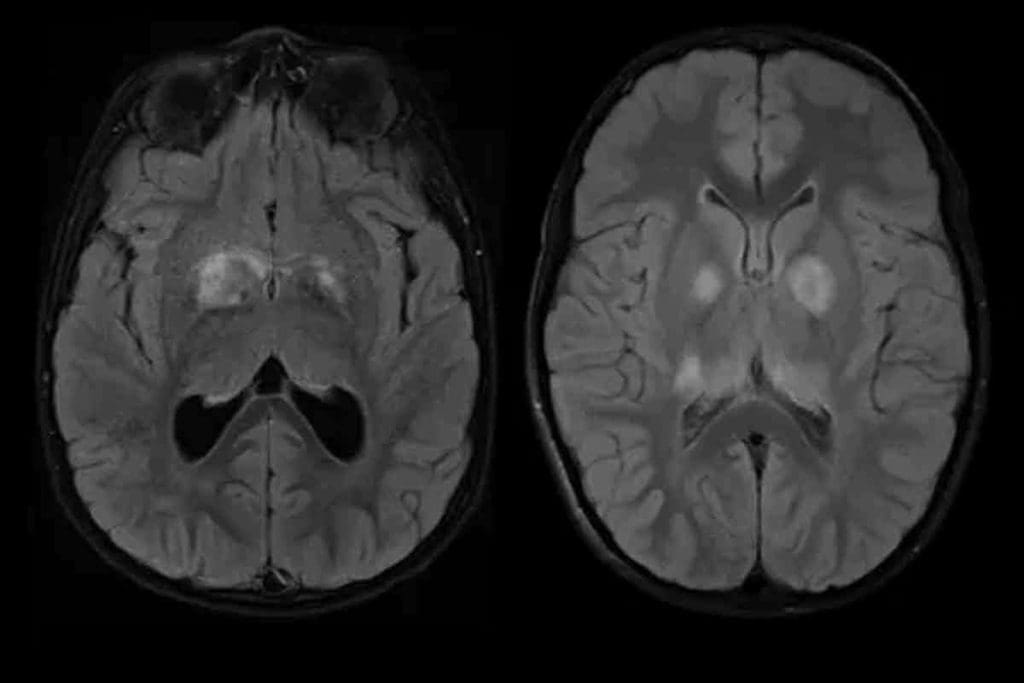

Active surveillance means regular MRI scans to check the tumor’s size and growth. This way, doctors can step in at the best time. It balances the risks of treatment with the risks of the tumor growing.